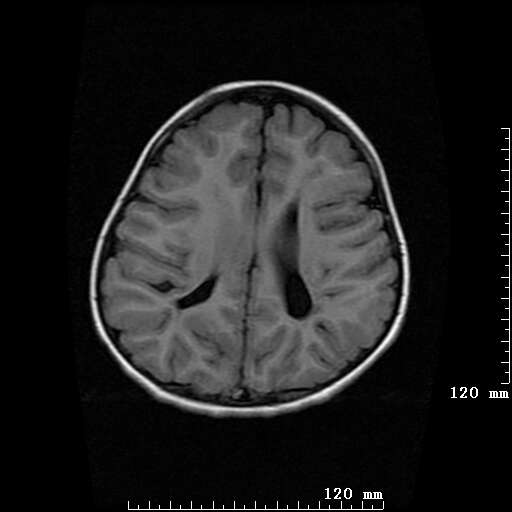

女,7岁,三岁才说话、走路。现智力尚可,走路不稳。临床怀疑大脑发育不全。

考虑 脑白质发育不良

脑折质变薄,双侧侧脑室稍扩张,支持考虑脑折质发育不良

侧脑室周围白质软化症。

考虑胼胝体发育不全,髓鞘形成不良。

支持考虑胼胝体发育不全,髓鞘形成不良。

脑裂畸形伴灰质异位

侧脑室周围白质数量减少,侧脑室不对称性扩大,左侧侧脑室后角呈方形改变,脑沟加深,结合临床考虑脑室周围白质软化症(pvl)。期待结果!

只看出灰质异位

支持脑白质发育不良。